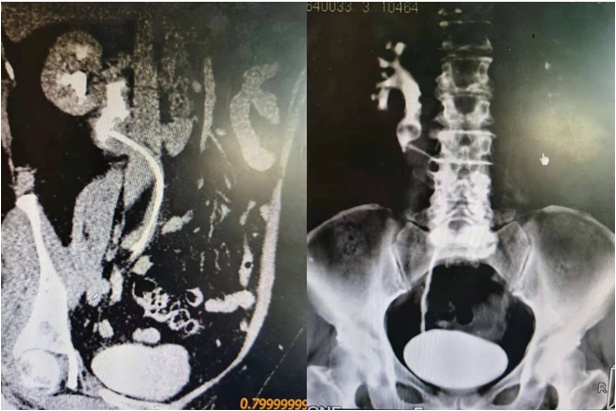

为进一步诊治,王阿姨来到同济大学附属同济医院泌尿外科就诊。罗华荣接诊后,查体发现王阿姨右肾区有叩击痛,CTU显示下腔静脉后输尿管伴近端输尿管扩张、肾盂积水,右侧输尿管内D-J管。阅CT、尿路造影考虑为下腔静脉后输尿管。门诊以“下腔静脉后输尿管”收入院。

CTU、尿路造影提示右输尿管中上段环绕于下腔静脉后方